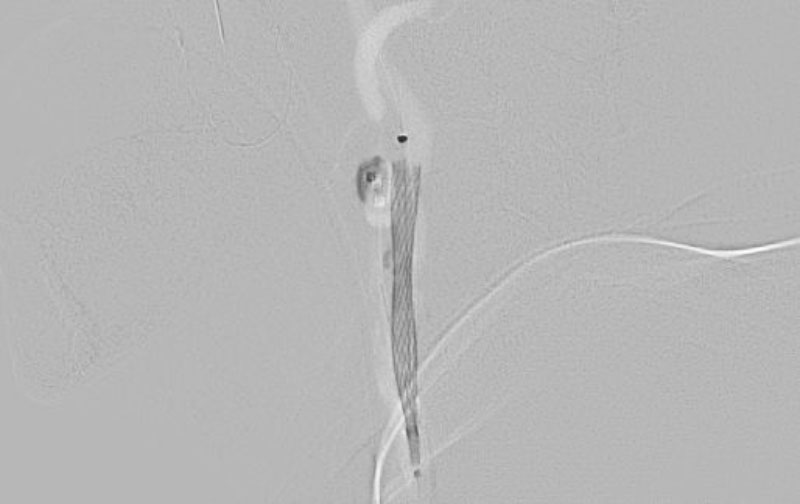

1314

'22年11月25日

右内頚動脈狭窄症

70代

院内外来

中

治療

後